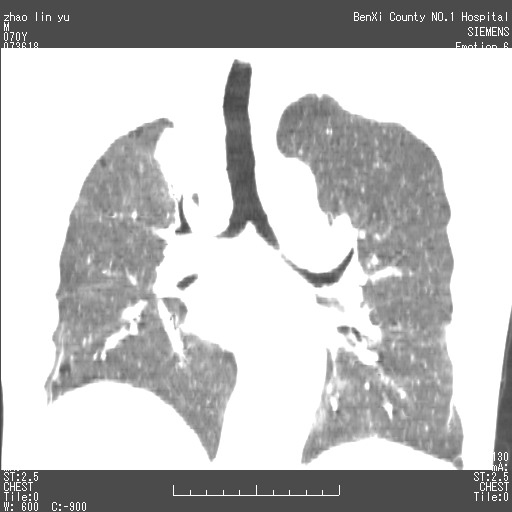

以下是引用王靖旗在2007-7-10 17:12:00的发言:[br] 男、70、咳嗽两个月,半年前换瓣手术,胸片未见异常,于昨天行x片发现右肺上野大片影,行ct扫描,这里是减薄图像,余肺正常。明天晚上会有增强扫描片,到时我会上传。[br][br] 冠状位请大家细看,应该是有意义的,[br][br] 请大家先看平扫发表意见。[br][br]

[br]冠状面[br]